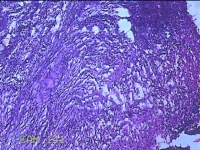

左侧卵巢囊肿⑴

性别

女

年龄

34岁

临床诊断

左侧卵巢子宫内膜异位囊肿

一般病史

下腹痛3小时入院。

标本名称

大体所见

灰白暗红色囊性肿物8x2.5x0.7cm一个,表面糜烂,部分已切开,囊内容物已流失,囊壁厚0.1cm。